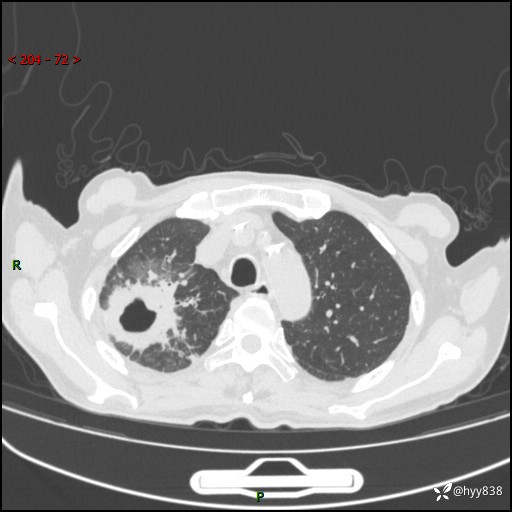

一个月后第二次CT检查(常规抗感染,患者不配合:增强、住院---)